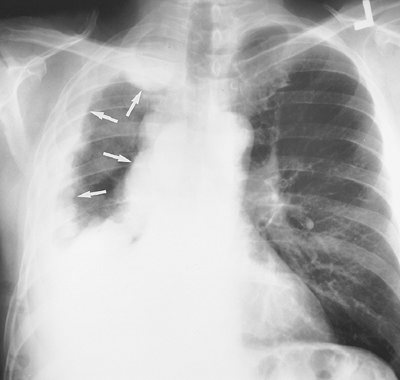

Malignant mesothelioma is a relatively rare primary tumor of the pleura. Approximately 80% of these lesions occur in individuals who have been exposed to asbestos (19). The lifetime risk for the development of mesothelioma in asbestos workers approaches 10%, and the average latency period is 35 years (20). Radiographic and CT findings include

P.148

nodular or irregular thickening of the visceral and parietal pleura, variable ipsilateral volume loss in the hemithorax, ipsilateral pleural effusion, involvement of the interlobar fissures and mediastinal pleural surfaces, and often fixation of the mediastinum (Figs. 9-18, 9-19, 9-20) (21). Approximately 18% of cases are associated with invasion of the chest wall (21).

FIGURE 9-18. Malignant mesothelioma. PA chest radiograph of a 53-year-old man shows right pleural opacification with a lobulated contour that involves the entire pleural surface (arrows) and is associated with a "fixed mediastinum," meaning no shift right or left, and ipsilateral loss of lung volume, characteristic of malignant mesothelioma.